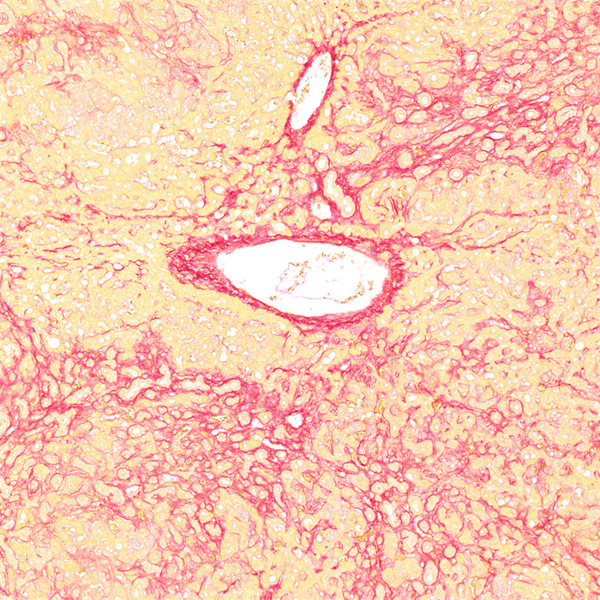

天狼猩红和KWS都是强酸性染料,易与胶原分子中的碱性基团结合,吸附牢固。偏振光镜检查,胶原纤维有正的单轴双折射光的属性,与KWS-天狼猩红结合,可增强双折射,提高分辨率,从而区分两型胶原纤维。未脱钙骨组织切片经天狼猩红染色后,普通光学显微镜下,胶原纤维呈红色或鲜红色,其他呈黄色;在偏振光显微镜下,Ⅰ型胶原纤维呈强橙黄色或亮红色,Ⅲ型胶原纤维呈绿色。

<天狼星红-肝>